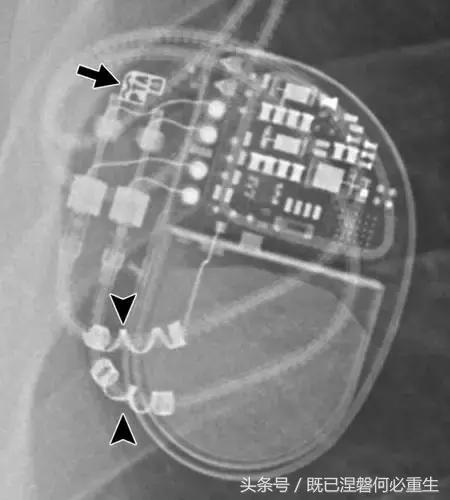

用于将导线的近端部分固定到胸壁的导线固定件可以模拟损伤。扎带是通常位于锁骨和发生器之间并且可以压接引线的套囊(图8A和8B)。熟悉这种外观和通常的射线透射束缚的位置可以防止错误报告磨损的线索。

图。 8A在两个不同患者中电极断裂的电极结合物的实例。

图。 8B在两个不同患者中电极断裂的电极结合物的实例。

图。 9发生器引线断开。 移出的装置的放射线照片显示从末端完全退出的电极的外观(箭头)。 少数发电机没有容易识别的标志; 因此,制造商不能确定。

图10一名40岁女子的遗弃电极。 Medtronic发生器有两个端口(小箭头),但存在三个导联(一个心房和两个心室)。 对于传统的起搏器,有效导线的数量将等于或小于端口数量。 相对于端口的外部引线指示一个或多个引线被放弃。 因此,将端口数量与引线数量进行比较通常有助于识别丢弃的引线。 两个右心室导联之一以前发生故障,被放弃,而不是电极提取程序的风险并发症。 废弃的电极封盖(大箭头),以防止电气干扰。 未使用的端子也加盖并堵塞。

图11 Medtronic Revo MRI兼容起搏器。 该设备可以通过设备说明符或公司标志(箭头)上方的曲线线和围绕引线近端方向(箭头)缠绕的金属密度,被识别为Medtronic公司的MRI兼容系统。 不同的公司可能将不同的标识符合并到未来的设备中。